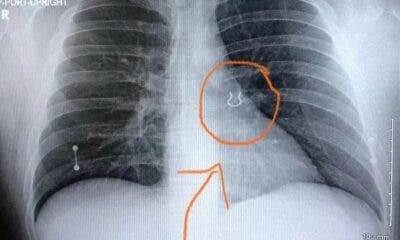

O trabalhador braçal Josian Passos, 37 anos, natural da cidade de Sena Madureira, vem atravessando há meses momentos difíceis. Ele enfrenta uma doença cujo diagnóstico ainda...